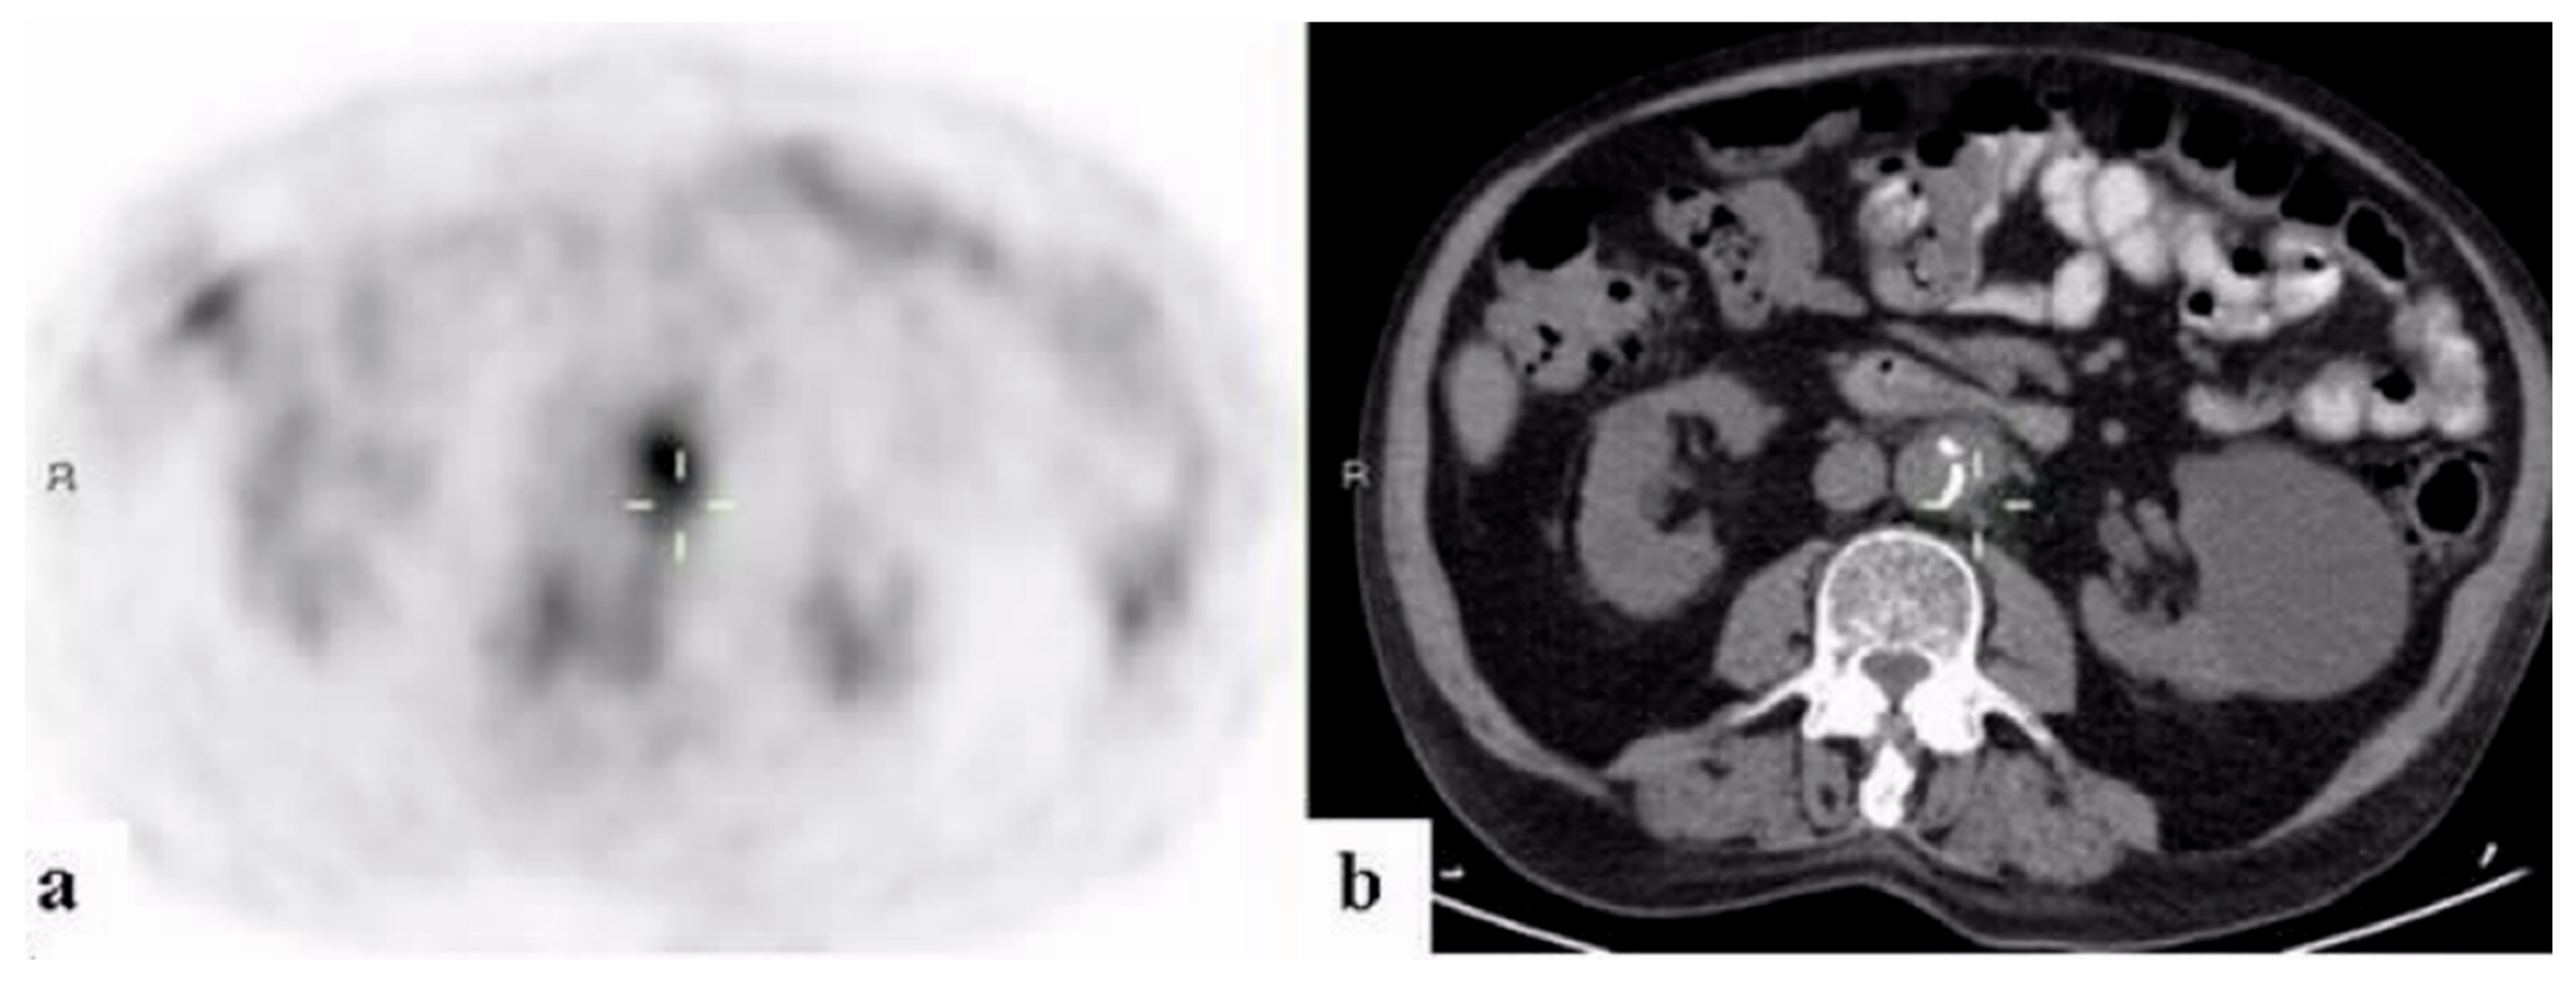

3.3. Contribution of 18FDG-PET/CT to FUO Workup

3.4. 18FDG-PET/CT Contributiveness According to Disease Category